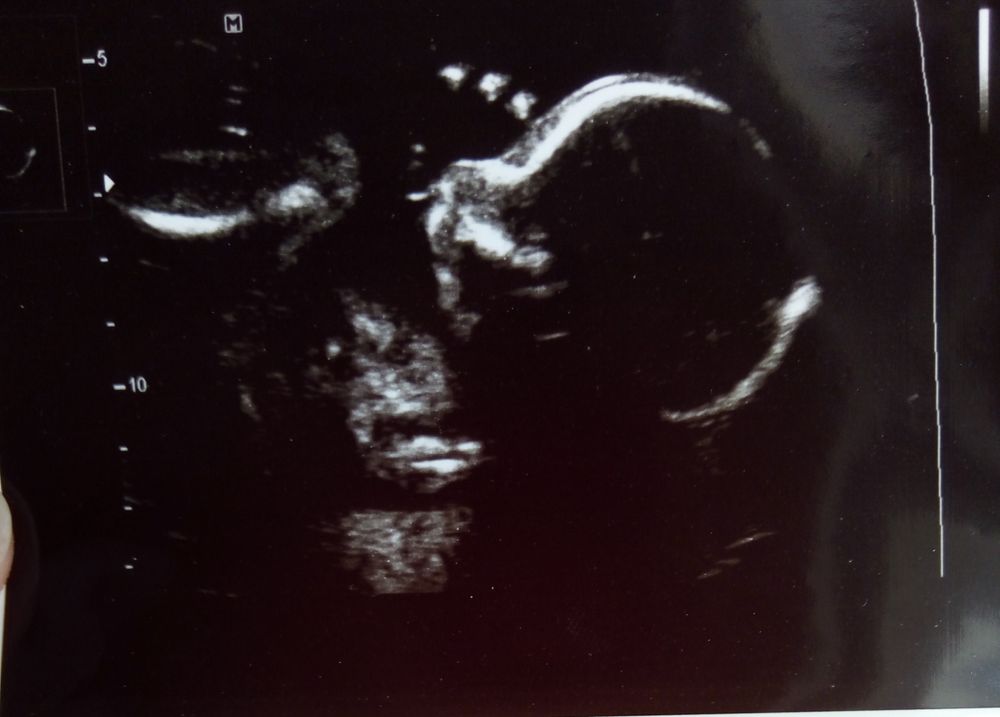

Девочки, посмотрите пожалуйста УЗИ фото, нет ли там намёка на СД?

Всё о нашей беременностиУЗИ в 20 недель фото в комментариях

Ну по картинке вам не скажут, тут нужны замеры, и нужно с первого скрининга показатели воротникового пространства.